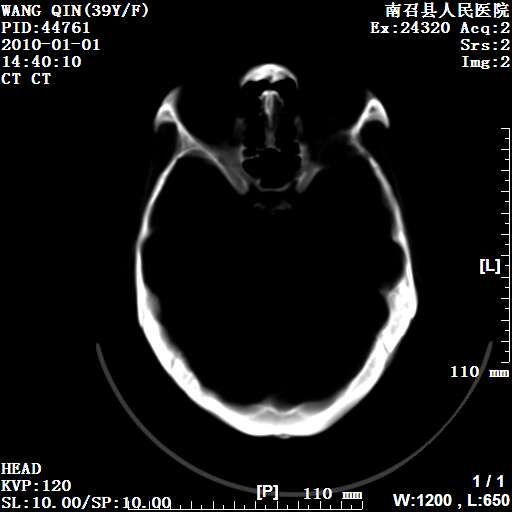

以下是引用随光逐影在2010-1-22 9:03:00的发言:[br]考虑左侧中颅窝(蝶骨翼区)脑膜瘤侵犯蝶骨翼并突入左侧眼眶。

以下是引用水过无痕在2010-1-22 14:55:00的发言:[br]一、定位:颅外占位;二、定性:恶性可能性大;三、组织来源:来源于左侧眼外直肌或其他部位;考虑为:横纹肌肉瘤>转移瘤>脑膜瘤.